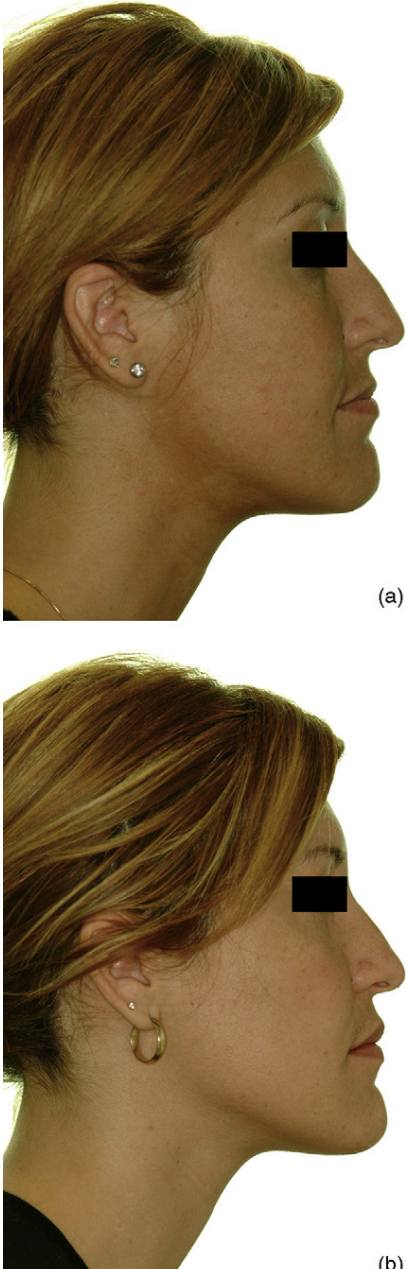

- This approach is usually paired with a projection rhinoplasty, where the surgeon grafts the dorsum, tip, and ANS. It is common in Asia and often gives great results. The extra nose projection pulls midface soft tissue forward, making the transition from the maxilla to the nose smoother whilst giving the illusion of forward growth.

The last example is especially impressive, earlier examples had grafts along the whole nose, this one used a single graft on the ANS and still pushed the nasal base forward, proof that you can fix ANS projection without touching the rest of the nose.

- The case below fits the criteria, the patients ANS and nose was fine in proportion to the rest of the face, but the maxilla sat almost vertical with little to none anterior facial depth. Advancing the lefort 2 block gave the missing anterior depth and transformed her frontal view.